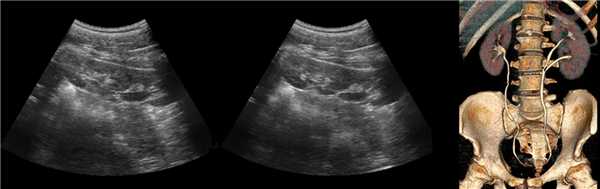

Рисунок. На УЗИ почечное ложе слева пустое (1). Обе почки расположены справа, срастаются полюсами (2, 3). Заключение: Аномалия взаиморасположения почек — I-образная удвоенная правая почка.

Рисунок. На УЗИ в малом тазу (мочевой пузырь — акустическое окно) определяются почки связанные узким перешейком (1, 3); дифференцировка паренхимы сохранена, кровоток прослеживается до капсулы (2, 3). Заключение: Аномалия взаиморасположения почек — сращение нижних полюсов тазово-дистопированных почек.